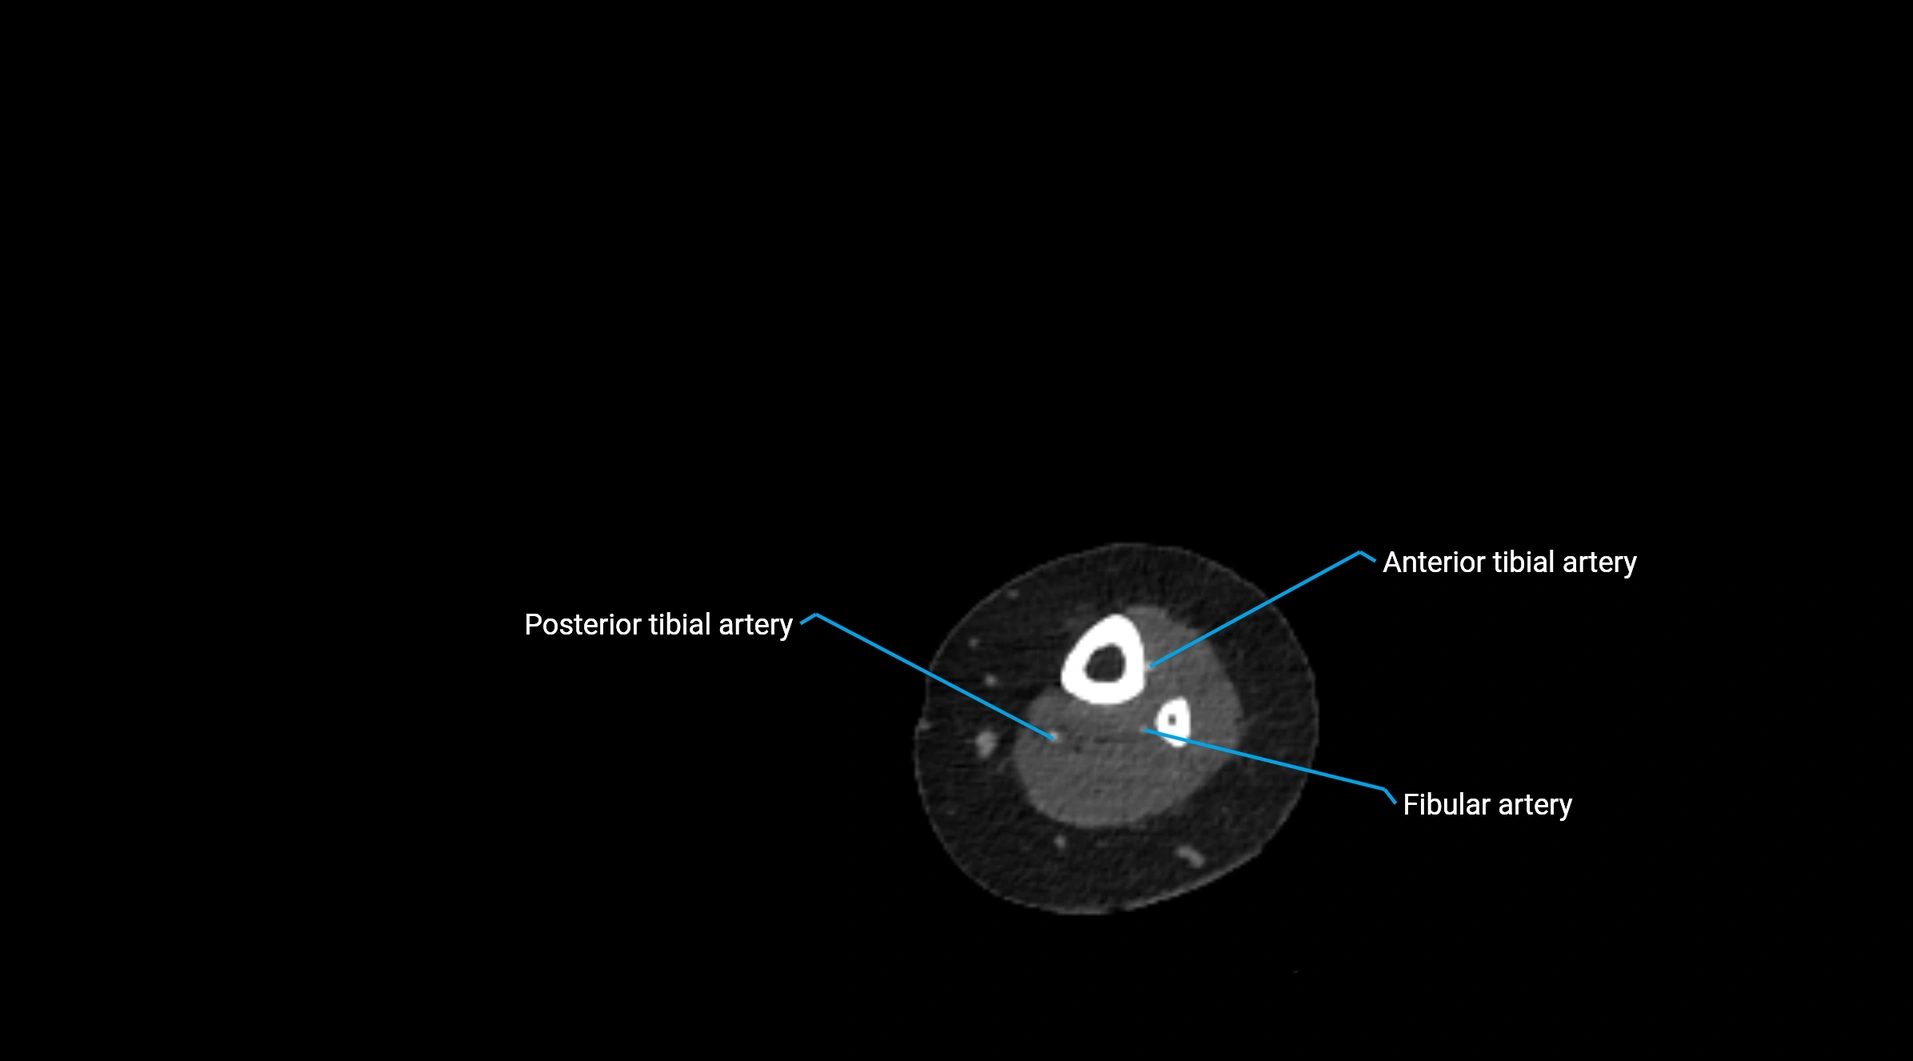

CT images

image